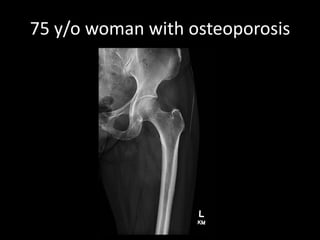

A 52-year-old man underwent a CT FDG PET fused PET/CT scan for a palpable lump. A 40-year-old woman with back pain received MRI scans including STIR, T1, and contrast images. Another patient, a 75-year-old woman with osteoporosis, also received imaging.